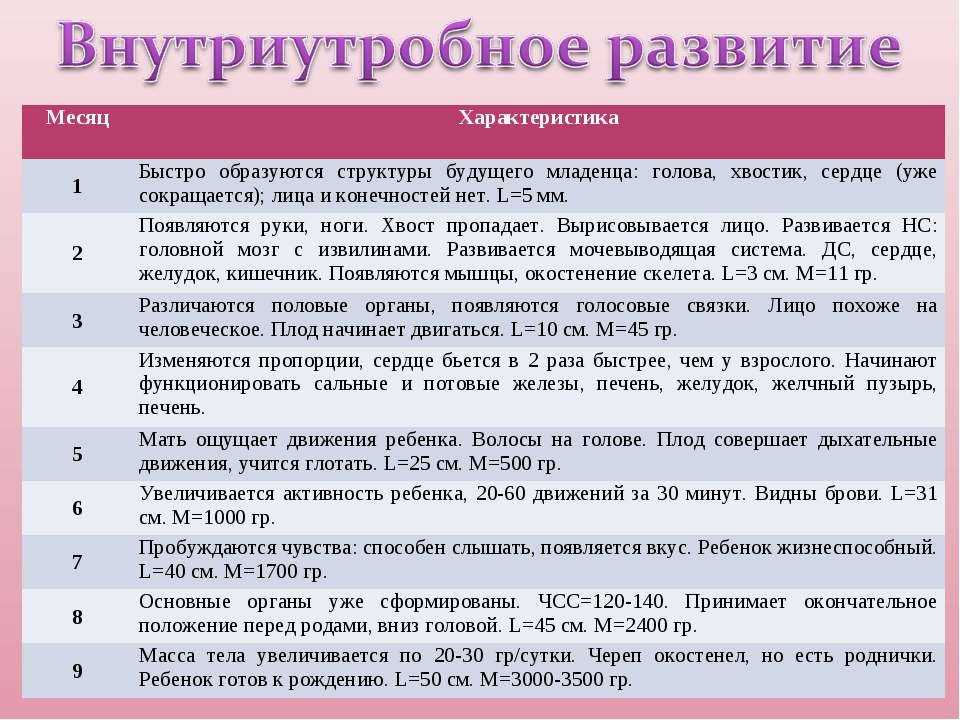

По окончании второго триместра будущая мамочка выходит на финишную прямую. Впереди только роды и счастливые годы материнства. Таких крупных перемен уже не будет, каждый следующий месяц ребенок будет все больше и больше готовиться к появлению на свет: набирать вес (в 9 месяцев ребенок весит – более 3 килограмм), сформируется его собственная система регуляции тепла, которая не даст ему замерзнуть при появлении на свет, окончательно разовьются легкие, чтобы позволить малышу легко перейти к новому виду дыхания.

16 недель. Ребенок весит примерно 150 граммов, его рост достигает 16-18 сантиметров. На головке появляются волосы, на лице — реснички и брови. Малыш открывает ротик, глотает, сосет, улыбается. В этот период начинает полноценно функционировать плацента, которая связывает его с мамой.

20 недель. Рост малыша достигает 30 сантиметров, у него появляются ноготки на пальцах рук и ног. Теперь мама чувствует его движения, так как время от времени он начинает заниматься физкультурой: отталкивается от одной стенки матки и доплывает до другой. Кроме того, ребенок может отреагировать на резкий звук или волнение матери прыжком, который воспринимается как активное шевеление. Если же малыш начинает икать, женщина ощущает слабые ритмичные толчки, идущие изнутри. В 20 недель врачи выслушивают сердцебиение малыша с помощью стетоскопа.

24 недели. Малыш уже может рассердиться. Это доказывает фотография ребенка в этом возрасте. На ней видны его сердитый взгляд, напряжение мышц вокруг глаз, сморщенные губки, видно, что он плачет, выражая свое недовольство. Кстати, чтобы отдохнуть ночью, малыш ложится спать и… видит сны. Ребенок весит около 500 граммов это немного, но он только начал набирать вес. Его кожа красная и морщинистая. Так как она еще очень нежна, малыш защищается от воздействия околоплодных вод специальной смазкой. К 24-й неделе беременности начинают функционировать жировые и потовые железы, созревают легкие ребенка. В них образуется пленка, которая не дает им склеиваться при дыхании. Если ребенок родится в это время и будет обеспечен необходимой заботой, он сможет выжить.

8-й месяц: 29-32 недели

С каждым днем ребенок все больше и больше подготавливается к предстоящей жизни вне организма мамы и родам. Он уже весит около 1,5-1,6 килограмма и достигает в длину 40 сантиметров. Сейчас он занимает почти все место в матке, поэтому движения его очень рациональны. Он уже не «плавает», а совершает более точные движения ручками и ножками.

В течение 8-го месяца ребенок занимает то положение, в котором он будет в родах.

В 96% случаев – это головное предлежание – то есть ребенок располагается строго головой вниз, бывает также тазовое предлежание – когда он занимает позицию попкой или ножками к выходу из малого таза, а также поперечное предлежание – когда он лежит поперек продольной оси матки.

Самым лучшим для естественных родов, конечно, является головное предлежание, но на 8-м месяце предлежание ребенка еще может поменяться само или с помощью специальных упражнений. Однако, если он уже устроился (головное предлежание), можете одевать бандаж, чтобы закрепить такое положение.

Ваш доктор, используя специальные приемы пальпации – приёмы Леопольда, может очень легко определить положение плода.

На 8-м месяце продолжают формироваться альвеолы легких, увеличивается количество сурфактанта.

Почти полностью формируется сердце и кровеносная система: между правым и левым предсердием пока остается отверстие (баталлов проток), поэтому в венах и артериях ребенка течет смешанная кровь. Это отверстие закроется уже после рождения.

10-й месяц: 37-40 недель

Не переживайте если ребенок не родился на 9-м месяце, у него еще есть время. Рождение в 37-42 недель абсолютно естественно и нормально. Вы должны довериться в этом ребенку и своему мудрому организму, они сами подберут наилучшее время.

Итак, на 10-м месяце все системы ребенка готовы к рождению. Работает пищеварительный тракт: ворсинки кишечника продвигают первородный кал вниз к толстому кишечнику, работает желудок, поджелудочная железа вырабатывает пепсин, необходимый в пищеварении.

Однако пищеварительная система ребенка в утробе абсолютно стерильна, все нужные бактерии, которые помогают переваривать и усваивать пищу появятся только в период лактации из грудного молока матери.

Заканчивает развитие половая система – у девочек большие половые губы закрывают маленькие, у мальчиков яички в большинстве случаев опускаются в мошонку.

Надпочечники настолько увеличиваются в размерах, что становятся больше почек, так как на их долю приходится выработка гормонов стресса во время родов – адреналина и норадреналина.

Кости черепа и швы остаются мягкими и податливыми. 2 родничка – теменной и затылочный помогают черепу принять удобную форму, чтобы пройти по родовым каналам матери без травм.